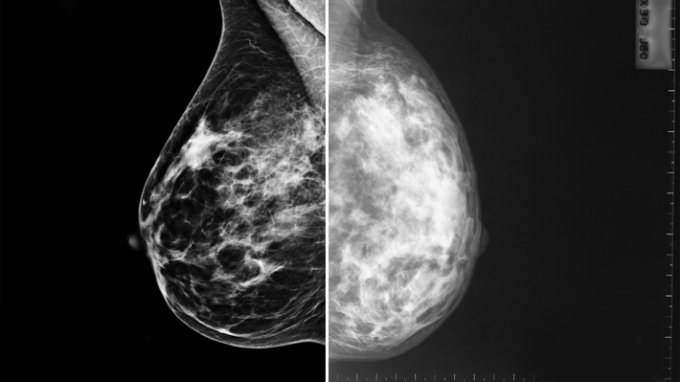

Magyarországon átlagosan minden tizenegyedik nő mellében alakul ki rosszindulatú daganat, és évente mintegy 2300 nő hal meg mellrák miatt. A hazai tapasztalatok azt mutatják, hogy a szervezett szűrésekre csak az érintett korú nők fele megy el. Pedig a szűrésen való megjelenés életeket menthet, ugyanis az időben felfedezett mellrákos esetek 80 százaléka meggyógyítható.